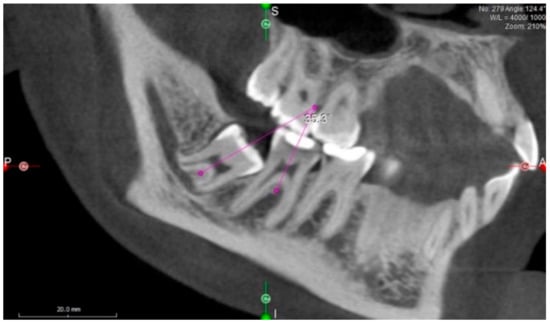

Mesial angulation of ITM with adjacent second molars was assessed by drawing the axial lines of these teeth through their radiological center of occlusal surface and furcation and measuring the mesiodistal tipping angle between them (irrespective of the tooth buccolingual position) (Figure 1).

Figure 1.

Measurement of impacted third molar angulation. Mesial angulation of impacted third molars (ITM) to second molars was assessed by drawing the axial lines of these teeth through their radiological center of the occlusal surface and furcation and measuring the angle between them.